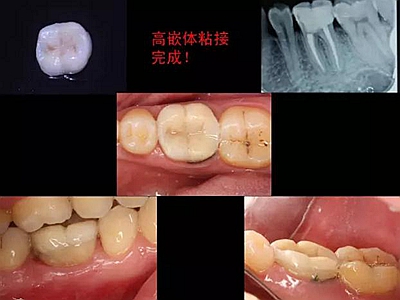

一周后拆除縫線,試戴高嵌體,試戴合適后雙固化粘結(jié)。調(diào)合,拋光。

冠延長(zhǎng)手術(shù)和高嵌體修復(fù),本來(lái)需要很多次復(fù)診的患者,兩次就診,就把患者難以處理的問(wèn)題輕松解決了。減少了患者的就診次數(shù)和時(shí)間。

最后附幾例一次性根管治療+冠延長(zhǎng)手術(shù)+高嵌體修復(fù)的病例,均為兩次完成。第一次就診:根管治療一次完成,后冠延長(zhǎng)手術(shù),然后高嵌體預(yù)備,取模,第二次就診,拆線,試戴嵌體。具體在此不做詳細(xì)說(shuō)明,圖中有詳解。